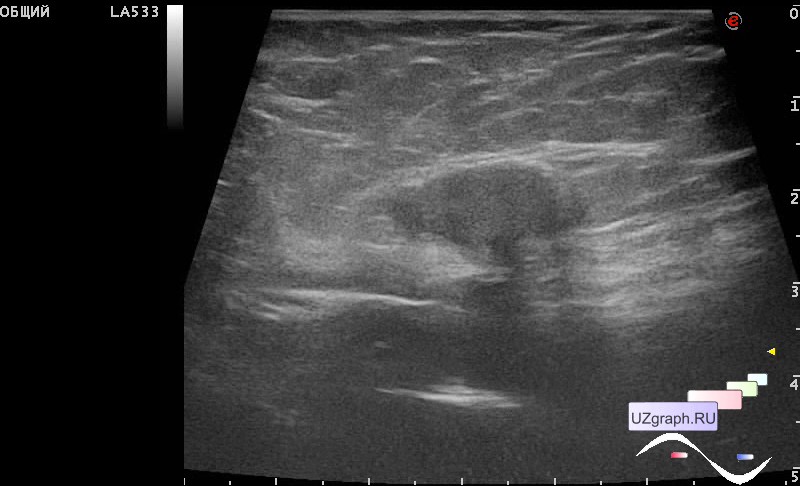

Особенности УЗИ при определении пола ребенка

Раздел: Идеи и советы